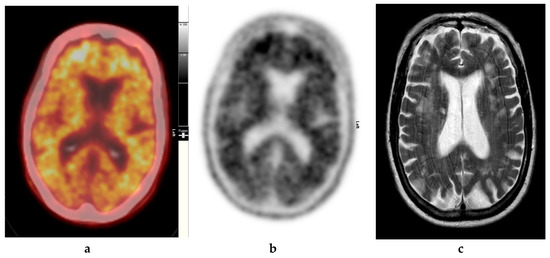

Figure 3.

Abnormal study. Seventy-four year old male patient with a history of short term memory problems/gradual memory decline for some time and a query of dementing pathology. (a) and (b) [18F]FBP shows loss of contrast between grey and white matter in all sections of the brain. The scan is suggestive of beta-amyloid plaque deposition and in a patient with the above clinical presentation is suggestive of early AD. (c) MRI brain scan (multiplanar and multi sequence acquisitions) with some motion artefact shows generalised age appropriate cerebral atrophy, proportionate symmetrical temporal lobe atrophy, and corresponding dilatation of the cerebrospinal fluid (CSF) spaces. Moderate to marked periventricular T2 white matter hyperintensities likely to represent chronic small vessel ischemic changes. No diffusion restriction or space occupying lesions were identified. (Figures are courtesy RLBUHT Hospital database.).